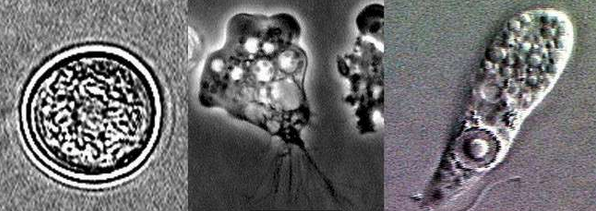

▼14.幾乎在世界各地都有人遇到。一種被稱為福氏耐格里阿米巴變形蟲,牠們會侵入人的大腦並寄生,患者的病死率高達95%。